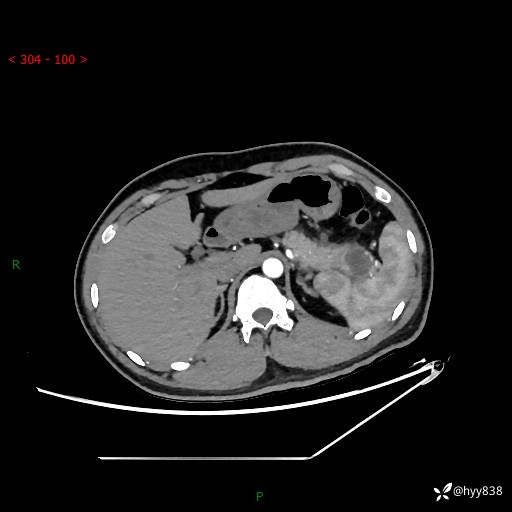

【患者信息】:31岁/男

【主诉】:间断性左下腹疼痛10天

【现病史及既往史】: 患者10余天前无明显诱因出现左下腹部疼痛,呈间断性,无恶心,呕吐,无黄疸,腹泻症状,于当地医院就诊,行腹部C提示:胰腺尾部占位。2型糖尿病。现患者为求手术治疗,门诊以“胰腺肿物”收入院。 患者起病来,一般情况可,大小便正常,体重体力未见明显减轻。

【检查】:胰腺CT平扫+增强